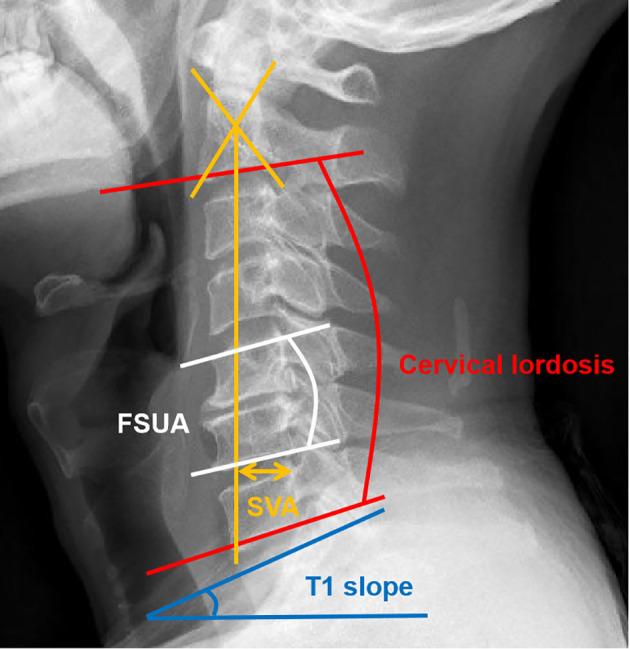

Visible FI was identified in 69.1% of patients (76/110), with a propensity in elderly patients (p = 0.053). No statistically significant differences were presented among the three groups regarding pre- and postoperative clinical evaluation scores. The cervical lordosis was significantly higher in the normal group before surgery (p = 0.029). Likewise, the sagittal vertical axis (SVA) was significantly higher in the severe group than the normal group at the final follow-up (p = 0.046). The function spine unit angle and disc angle of arthroplasty levels were significantly lower in the severe group than the normal group at follow-ups. Moreover, after correction according to vertebral body area, no statistically significant relationship existed between CSA ratio and FI grade.

CPM degeneration is common and age-related in patients with cervical disc degenerative disease. More importantly, there was a significant positive correlation between severe FI of CPM and postoperative sagittal balance disorder, particularly in C2-7 SVA and segmental alignment of arthroplasty level. Meanwhile, FI of CPM appears to have no impact on clinical outcomes and reveals small correlations to CSA.

69.1%(76/110)的患者存在明显的 FI,老年患者中更为明显(p = 0.053)。三组患者的术前和术后临床评估评分无统计学差异。正常组患者术前颈椎前凸明显更高(p = 0.029)。同样,终末随访时重度组 SVA 明显高于正常组(p = 0.046)。重度组患者的功能脊柱单位角和置换节段椎间盘角在随访时明显低于正常组。此外,根据椎体面积校正后,CSA 比值与 FI 分级之间无统计学意义的相关性。

颈椎间盘退行性疾病患者的 CPM 退变是常见的,且与年龄相关。更重要的是,CPM 严重 FI 与术后矢状位平衡紊乱显著相关,尤其是 C2-7 SVA 和置换节段的节段性排列。同时,CPM 的 FI 似乎对临床结果没有影响,与 CSA 显示出较小的相关性。